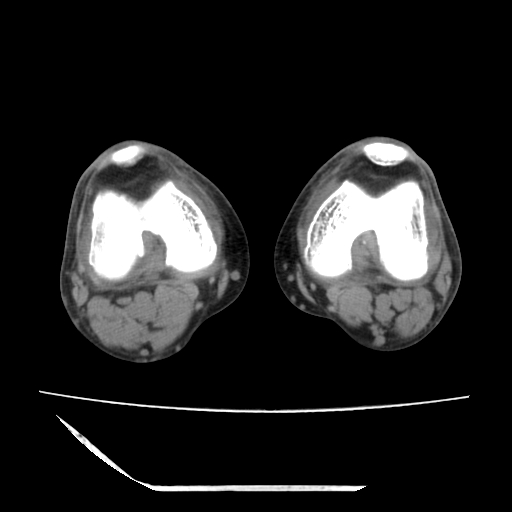

标题: CT13225:老年男性,左膝关节疼痛数月;请各位老师讨论。 [打印本页]

标题: CT13225:老年男性,左膝关节疼痛数月;请各位老师讨论。

骨质增生,骨性关节面硬化,关节积液,考虑退行性骨关节病

关节腔内少量积液,关节面退变。

双膝退变

骨质增生,骨性关节面硬化,关节间隙失常,关节积液,考虑退行性骨关节病.

骨质增生,骨性关节面硬化,关节积液,考虑退行性骨关节病。

这个病例诊断:退行性骨关节炎